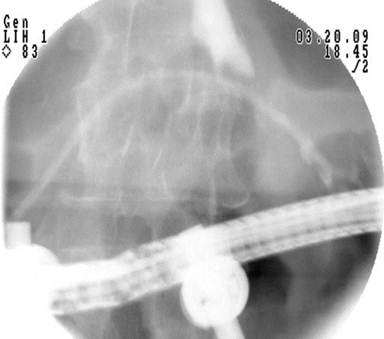

An additional two ports were placed in the right side; a 10/12-mm port in the subcostal position and a 5-mm port approximately 8 cm inferior to this. Since it was difficult to determine which limb was the afferent limb, a pediatric colonoscope was inserted transorally while observing intra-abdominally. The biliopancreatic limb was then identified. Following this, the bowel was easily drawn up to the abdominal wall through the right subcostal laparoscopic port. A longitudinal enterotomy was performed and tacked to the skin in the right subcostal area using four 3-0 silk sutures. A therapeutic-channel video duodenoscope (TJF-160VF, Olympus Corporation, Center Valley, PA, USA) was introduced into the enterotomy and advanced to the level of the major papilla, which was only approximately 20 cm from the enterotomy. Using portable C-arm fluoroscopy the pancreatic duct was easily cannulated and pancreatography was performed. The main duct was without obvious stricture. Extravasation of contrast was seen at the mid pancreatic duct (Figure 2). A hydrophilic guidewire was advanced beyond the leak to the tail of the pancreas. A 7-French, 12-cm pancreatic duct stent was placed across the leak (Figure 3). A pancreatic sphincterotomy was performed using a needle knife over the pancreatic duct stent. The bowel was then freed from the skin and the enterotomy was closed.

Figure 3. Radiographic image following placement of a 7Fr transpapillary stent across the pancreatic leak. |